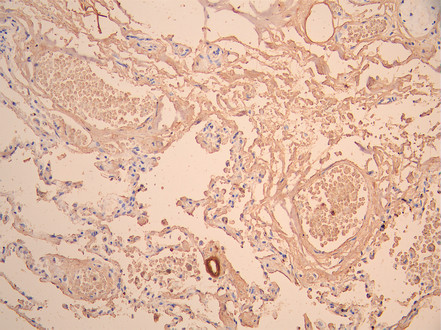

• IHC image of CSB-RA011626MA2HU diluted at 1:50 and staining in paraffin-embedded human lung tissue performed on a Leica BondTM system. After dewaxing and hydration, antigen retrieval was mediated by high pressure in a citrate buffer (pH 6.0). Section was blocked with 10% normal goat serum 30min at RT. Then primary antibody (1% BSA) was incubated at 4°C overnight. The primary is detected by a Anti-Human lgG, Fcy Fragment Specific labeled by HRP and visualized using 0.05% DAB.